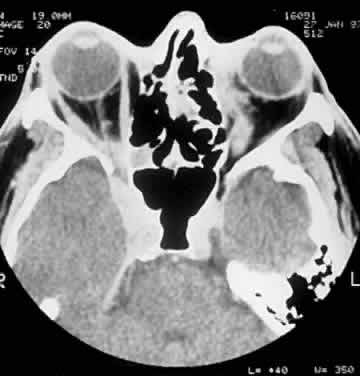

Computed tomography (CT) accurately demonstrates the molding of the mass to orbital structures, such as the globe and orbital bones, without bony erosion except in large cell lymphoma (Fig. 7). CT is used to localize the lesion, which tends to be unilateral and in both the intraconal and extraconal spaces. Lesions limited to the conjunctiva tend to be more benign with a better long-term prognosis, whereas those that extend into the orbit tend to be more malignant. Conjunctival lesions remain localized in 90% of cases, whereas orbital and lid lesions have a higher rate of systemic extranodal involvement.63 Lymphoid lesions of the lacrimal gland appear as a diffuse vertical expansion of the gland, which mold to both the globe and orbital bone without producing a bony fossa or erosion64 (Fig. 8). If the lesion extends beyond the orbital rim, the palpebral lobe of the gland is involved, and posterior or orbital lobe involvement appears as a straight line against orbital fat. Pleomorphic adenoma, on the other hand, appears as an oval, globular lesion with, in 80% of cases, adjacent bone changes caused by the firmer stroma of the tumor. Because epithelial tumors usually arise in the orbital lobe, extension beyond the orbital rim is not a feature.65 CT scan cannot distinguish between inflammatory and lymphoid lesions, because both lesions are homogeneous and enhance with intravenous contrast, and at biopsy, orbital lymphoid lesions are pink with a friable texture caused by the absence of stroma.66–68 The subtype and malignancy of the lesion can only be determined morphologically. The following subtypes of B-cell nonHodgkin's malignant lymphoma—extranodal B-cell marginal zone lymphoma, follicle center cell lymphoma, small lymphocytic lymphoma, lymphoplasmacytoid lymphoma, mantle cell lymphoma, large cell lymphoma, and Burkitt's lymphoma—are discussed in the approximate order of frequency with which they occur in the orbit.

Fig. 7. A CT scan, axial view, of the patient in Figure 6 showing molding of the lymphoma to adjacent extraocular muscle, globe, and medial orbital wall.